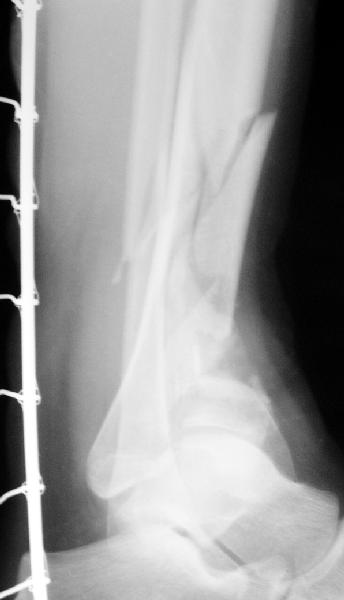

Вот что получилось

7.jpg

27KB (28411 bytes)

Пластинка красивая. Чуть только спереди назад идет, не сосем по оси большеберцовой кости. А там не маловато фиксаторов собственно в дистальном суставном конце кости? А вправляли его как? Как будто или осталось запрокидывание кзади или недонизведен передний край. Но с учетом исходного тяжелейшего повреждения - все равно здорово.